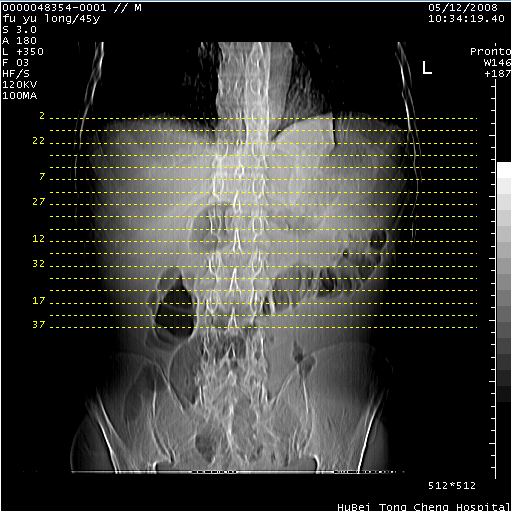

以下是引用lkc8963在2008-5-30 8:44:00的发言:[br]胃窦癌伴网膜(胃结肠韧带)/腹膜及腹膜后淋巴结转移.

以下是引用医影拾贝在2008-5-30 2:38:00的发言:[br]气肿性胃炎、胃十二指肠溃疡、腹膜炎,考虑穿孔可能性较大